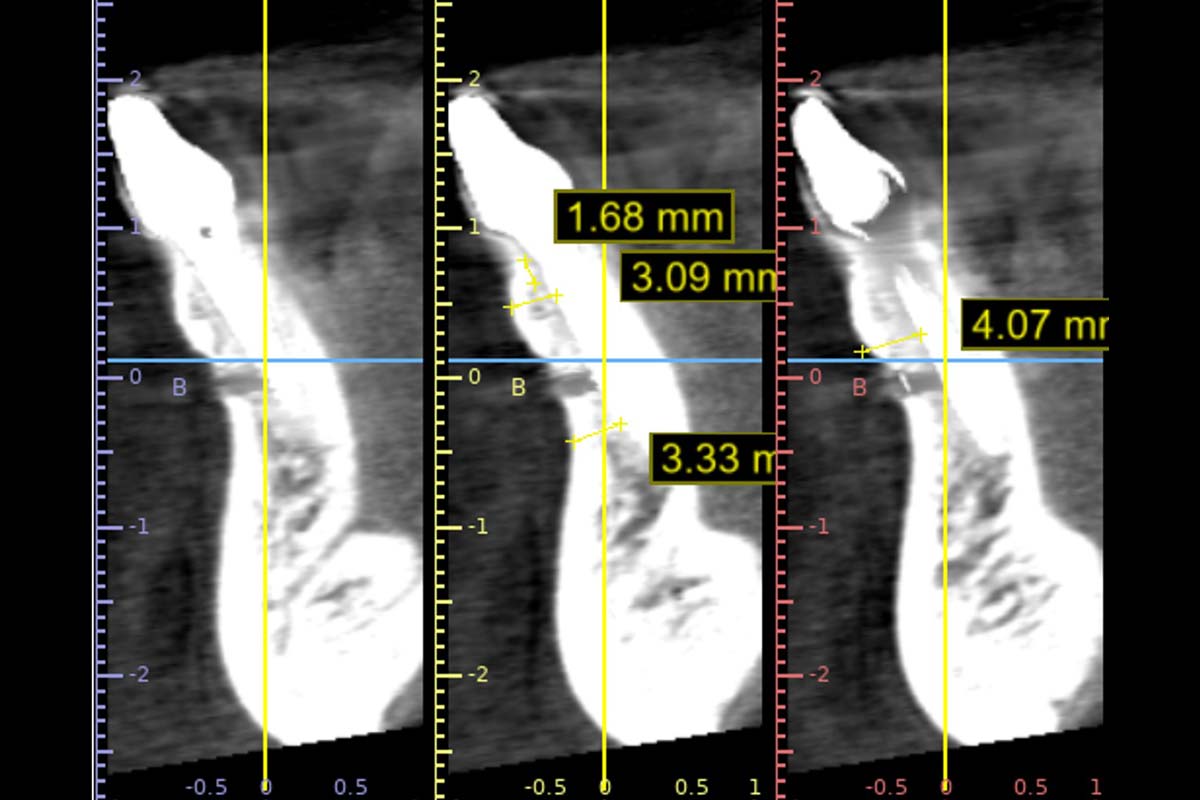

X-ray control before tooth extraction